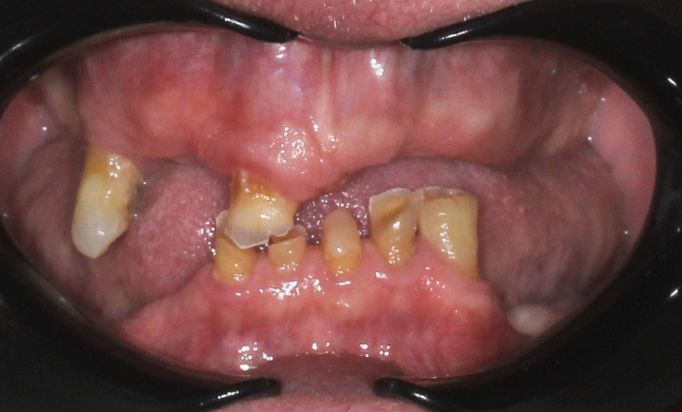

Dental Implants

Rebuild your smile, naturally

Achieve a seamless, natural-looking smile with dental implants.